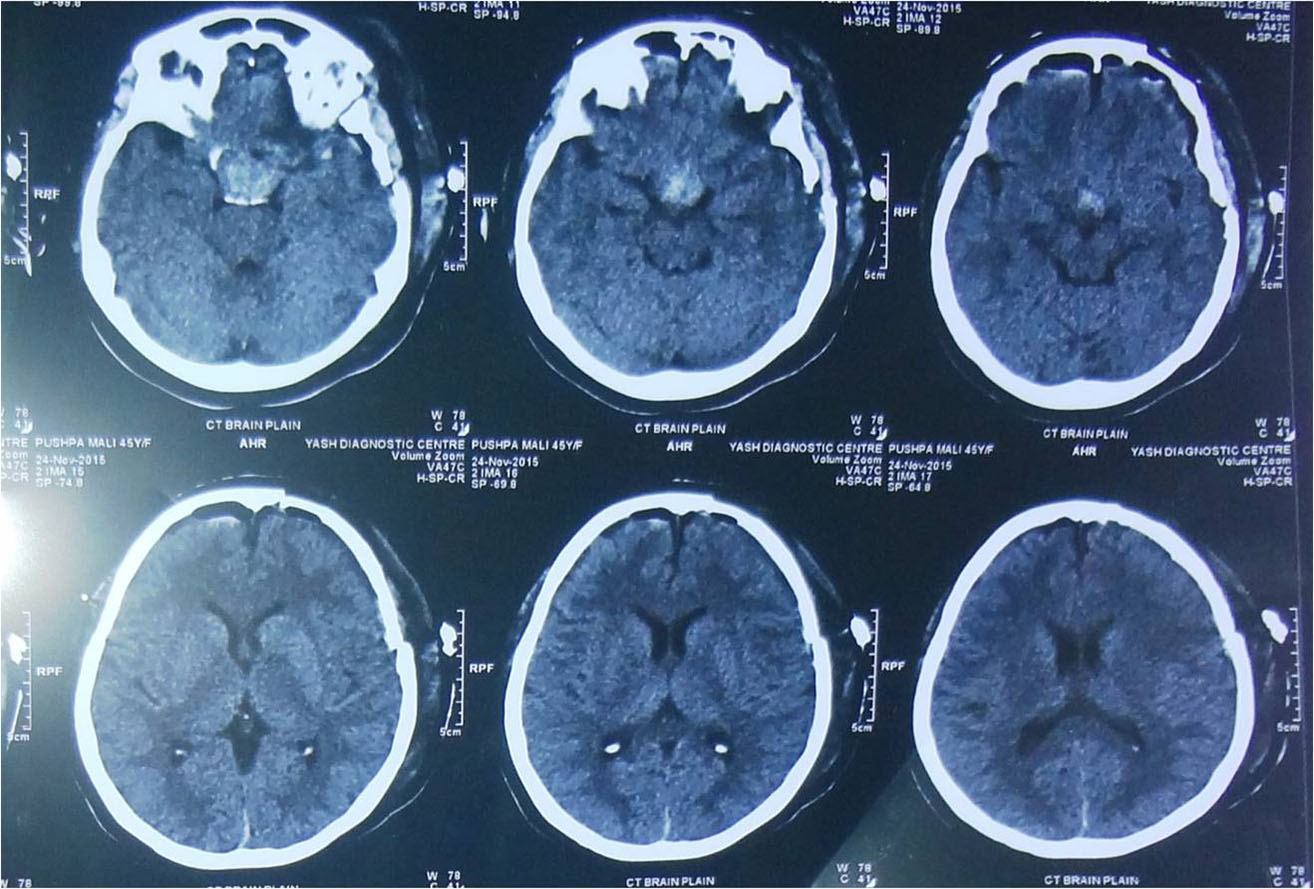

any of these symptoms he/ she should consult a neurosurgeon immediately. Usually CT Scan/ MRI of brain help

in the diagnosis. Most of the brain tumours can be safely treated by surgery but the treatment plan may vary